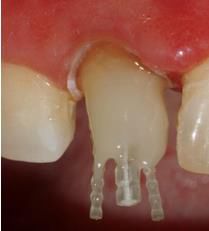

在操作的過程中要注意無菌操作,保證纖維樁的無菌狀態(tài)。推薦將樹脂核堆好之后再截?cái)嗬w維樁,而不是截?cái)嗪笤僬辰印H缦聢D: